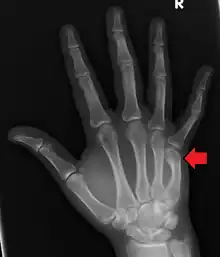

| Boxer's fracture of the 5th metacarpal head from punching a wall | |

A boxer's fracture is the break of the metacarpal bone of the hand near the knuckle at the base of the little finger.[2] Occasionally it is used to refer to fractures of the 4th metacarpal as well.[1] Symptoms include pain and a depressed knuckle.[3]

Classically, it occurs after a person hits an object with a closed fist.[2] The knuckle is then bent towards the palm of the hand.[4] Diagnosis is generally suspected based on symptoms and confirmed with X-rays.[4]